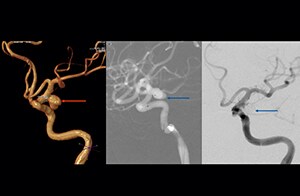

“Advances in MR imaging, the high SNR and spatial resolution of 3.0T, increasing observer experience and improved postprocessing techniques have improved the capabilities of MRA over the last decade. We found that 3D TOF MRA provides excellent images for the visualization of small cerebral aneurysms which enables us to accurately diagnose, and this accuracy appears to be similar to that obtained with DSA according to data from a 2014 study," [2] Dr. Li says.   “Aneurysm location can influence how easy it is recognized. Infundibula can mimic aneurysms, adding to the difficulty of interpretation. On MIP images, small aneurysms can also be easily misinterpreted when the aneurysm overlaps with the vessel. This is why in our method we are viewing the images from multiple angles.”   “In the hundreds of patients with aneurysms that we scanned, we saw no significant differences in accuracy, sensitivity or specificity among the locations. [2] We think this is the result of technical advances in image acquisition and postprocessing algorithms.”

According to Dr. Li, the good performance of MRA makes it a candidate to replace DSA. “We recommend that 3D TOF MR angiography would be an additional approach for patients with small cerebral aneurysms. This is due to its non invasive nature, ease of use and high degree of accuracy and sensitivity,” he concludes.